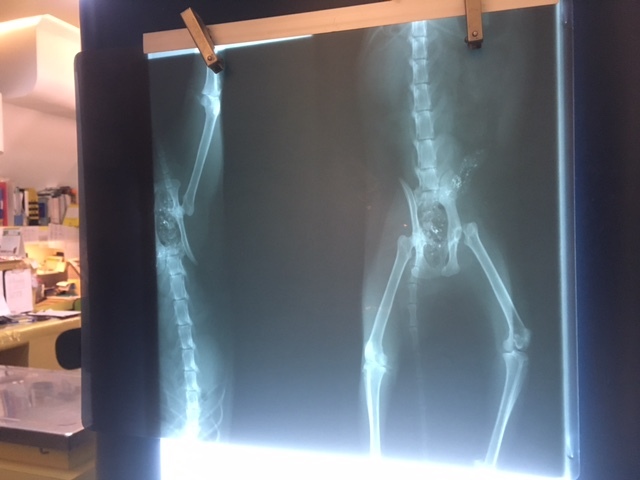

X光顯示左後腳髖關節脫位

血檢貧血PCV 22% 當天打了EPO造血針和鐵劑

5/19開刀切除脫位骨頭 也順便拔牙

術後再次拍X光確認手術後骨頭狀況

並且複驗血檢 PCV上升到34%